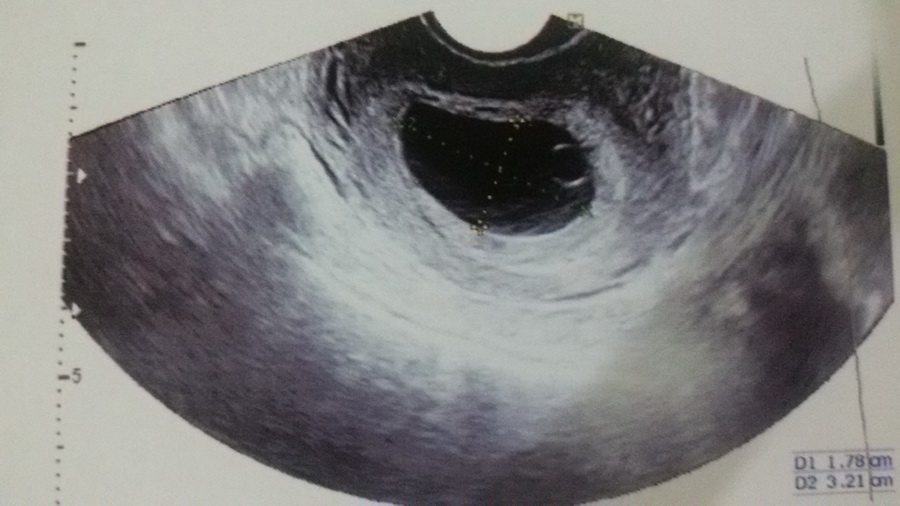

รูป U/S ครั้งล่าสุด

ผล U/S ทางช่องคลอด ครั้งที่ 3 วันที่ 21 ก.ย. เห็นถุงไข่แดง ทำให้เริ่มมีความหวังขึ้นมา

ครั้งนี้ (21 ก.ย.) ได้เจาะเลือดครั้งที่ 1 ฟังผลเลือดวันที่ 23 ก.ย. มีค่า BHCG 48,338 แล้วเจาะเลือดอีก ฟังผล วันที่ 28 ก.ย. ซึ่งผลเลือดมีค่า BHCG ลดลงเหลือ 45,971 แล้ว U/S ทางหน้าท้อง ซึ่งไม่เห็นตัวอ่อน หมอไม่ซาวด์ช่องคลอดแล้วค่ะ บอกผลชัดเจน ให้ยุติการตั้งครรภ์ ซึ่งนัดวันจันทร์ที่ 3 ต.ค. นี้